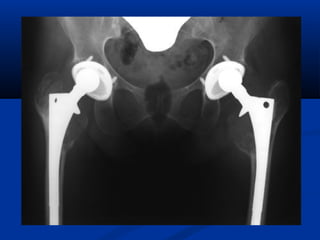

RRAADDIIOOGGRRAAFFIIAASS

 AAPP ddee ppeellvviiss ccoonn ccaaddeerraass ccoonn rroottaacciióónn

iinntteerrnnaa 155°°

 RRaaddiiooggrraaffííaa llaatteerraall ddee ffaallssoo ppeerrffiill

 PPeerrmmiittee vvaalloorraarr ppoossiicciióónn,, ttaammaaññoo yy ttiippoo

ddee aacceettáábbuulloo

 PPeerrmmiittee vviissuuaalliizzaarr llaa ccuurrvvaattuurraa ddeell fféémmuurr

 SSeelleecccciióónn lloonnggiittuudd ddeell iimmppllaannttee

 AAmmpplliittuudd ddeell ttúúnneell mmeedduullaarr